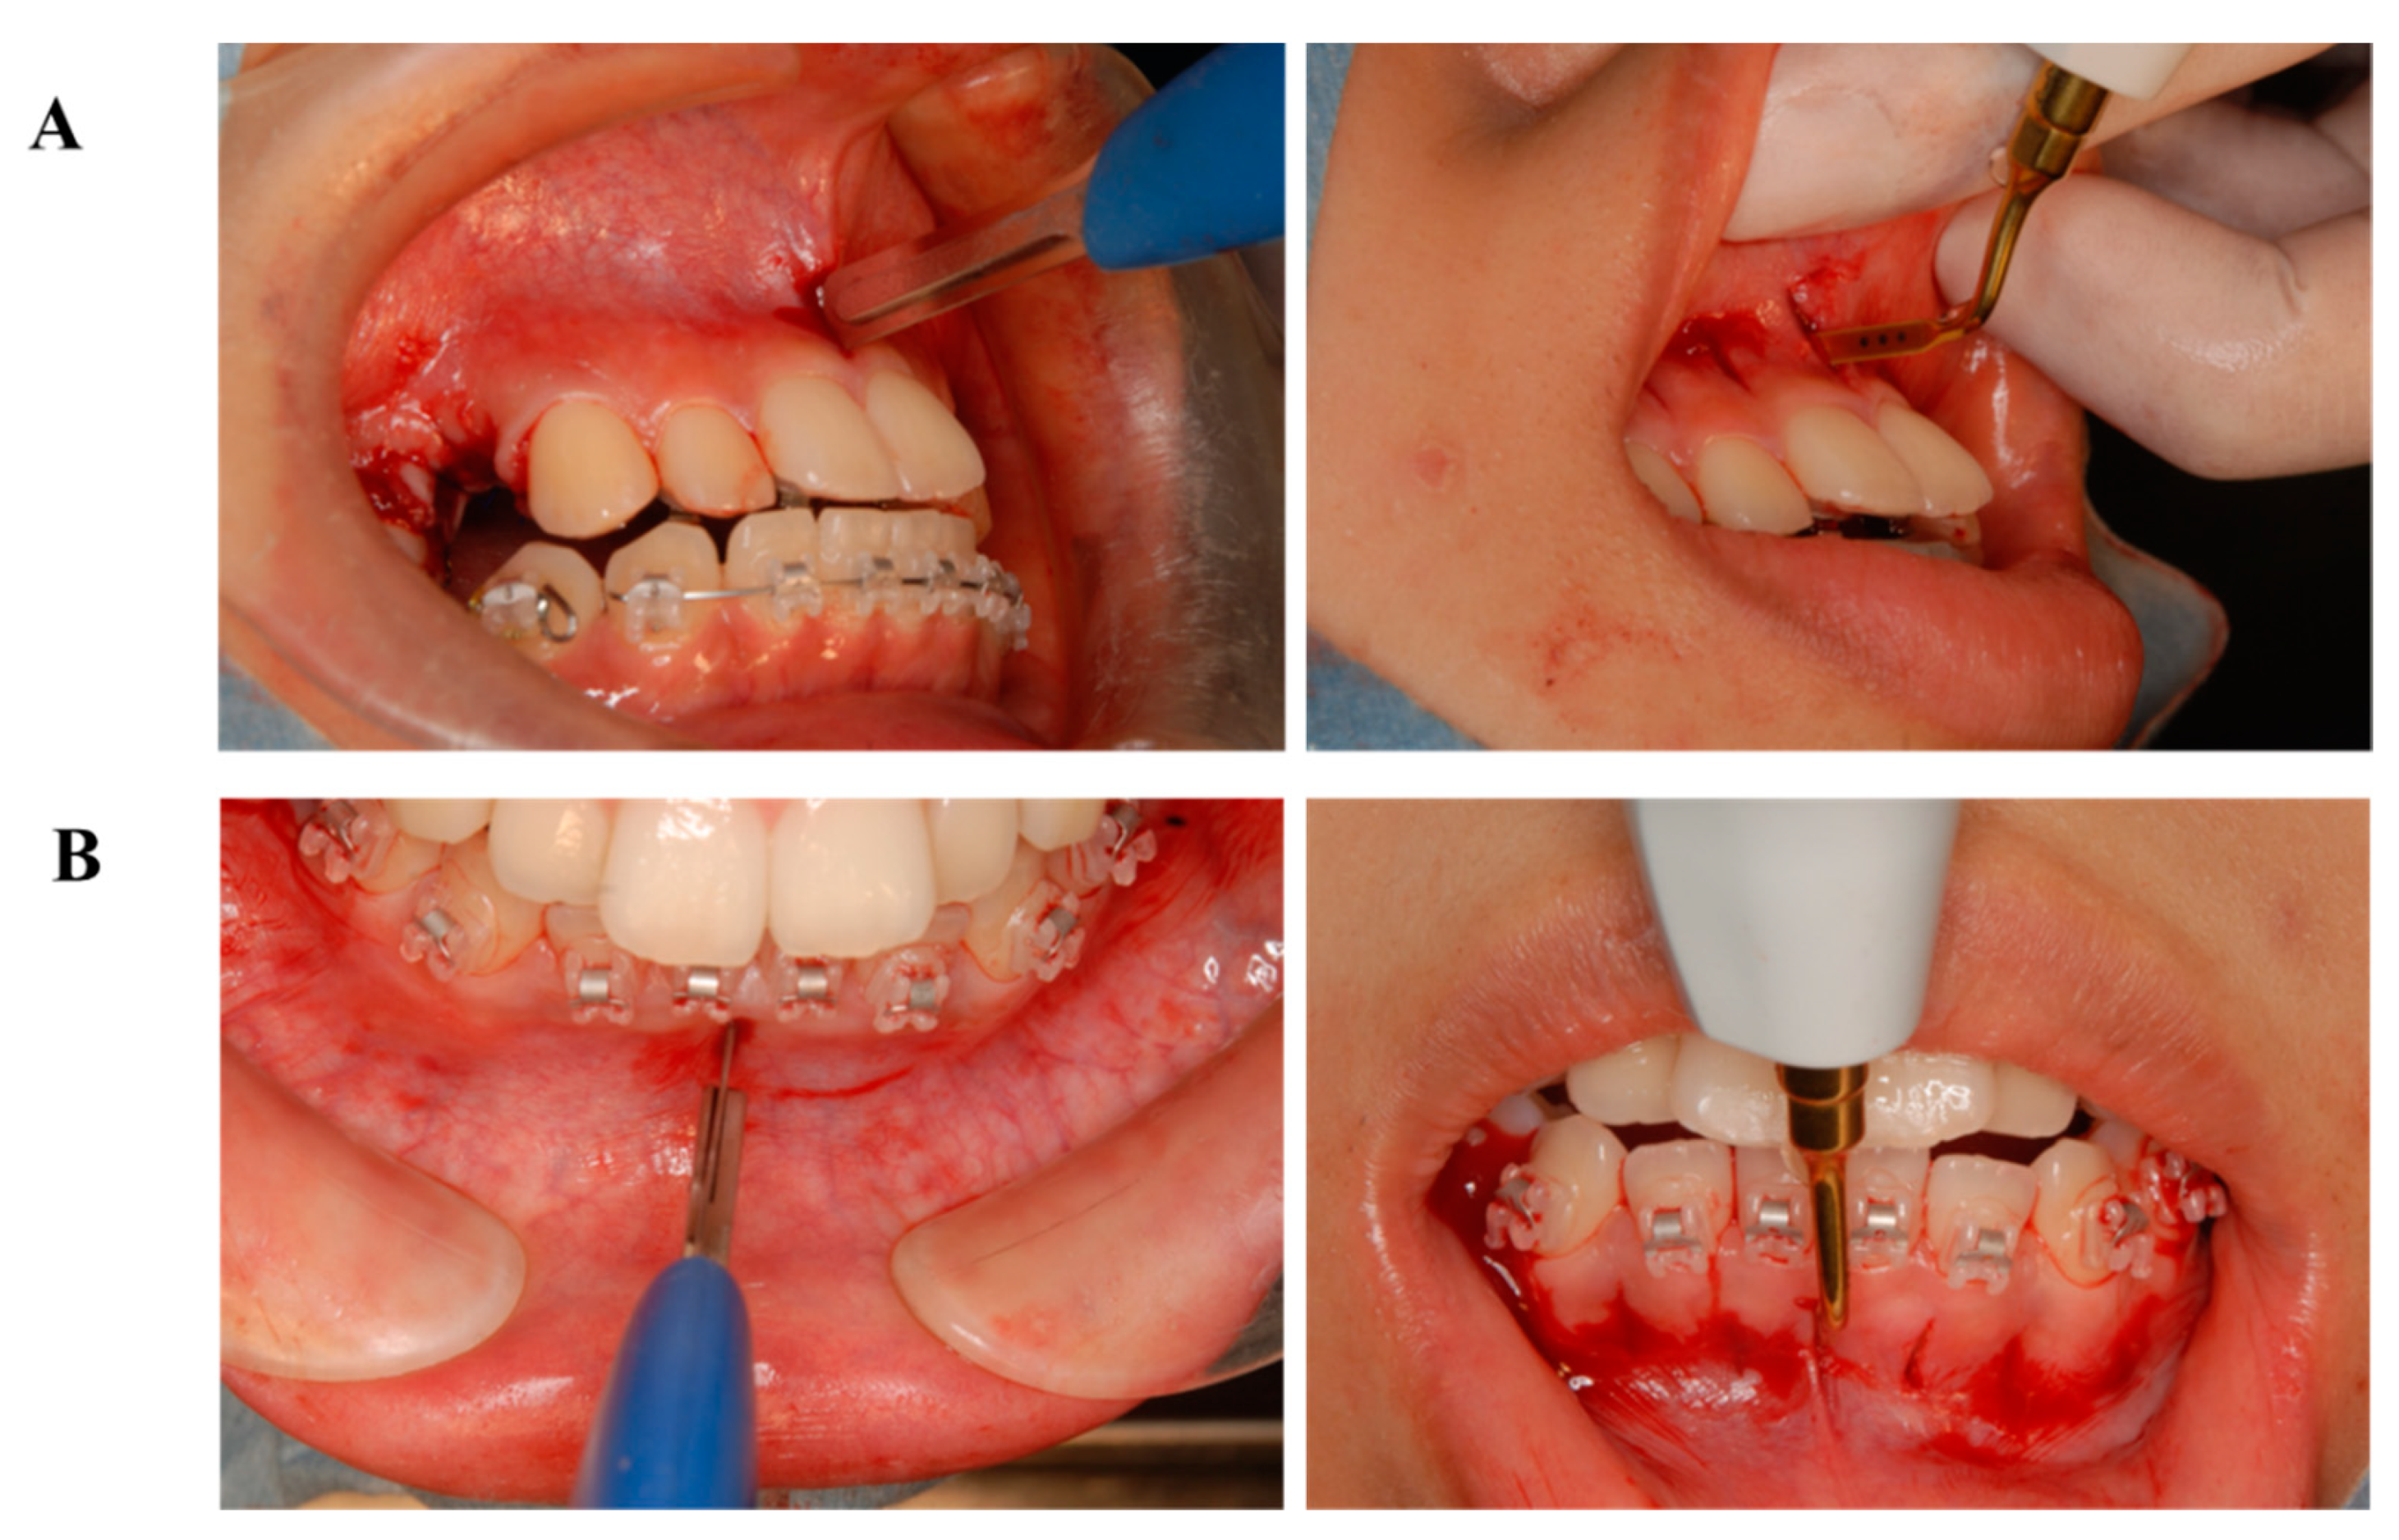

5. Accelerating Orthodontic Tooth Movement (AOTM) and Inflammation—Is Inflammation a Friend?

6.3. Treatment Alternatives

- Sugimori, T.; Yamaguchi, M.; Shimizu, M.; Kikuta, J.; Hikida, T.; Hikida, M.; Murakami, Y.; Suemitsu, M.; Kuyama, K.; Kasai, K. Micro-osteoperforations accelerate orthodontic tooth movement by stimulating periodontal ligament cell cycles. Am. J. Orthod. Dentofac. Orthop. 2018, 154, 788–796. [Google Scholar] [CrossRef]

- Yamaguchi, M.; Sugimori, T.; Imamura, R.; Kasai, K. Gene expression profiling of rat periodontal ligament on stimulating with micro-osteoperforations (Japanese). J. Jpn. Assoc. Adult Orthod. 2016, 23, 2–5. [Google Scholar]